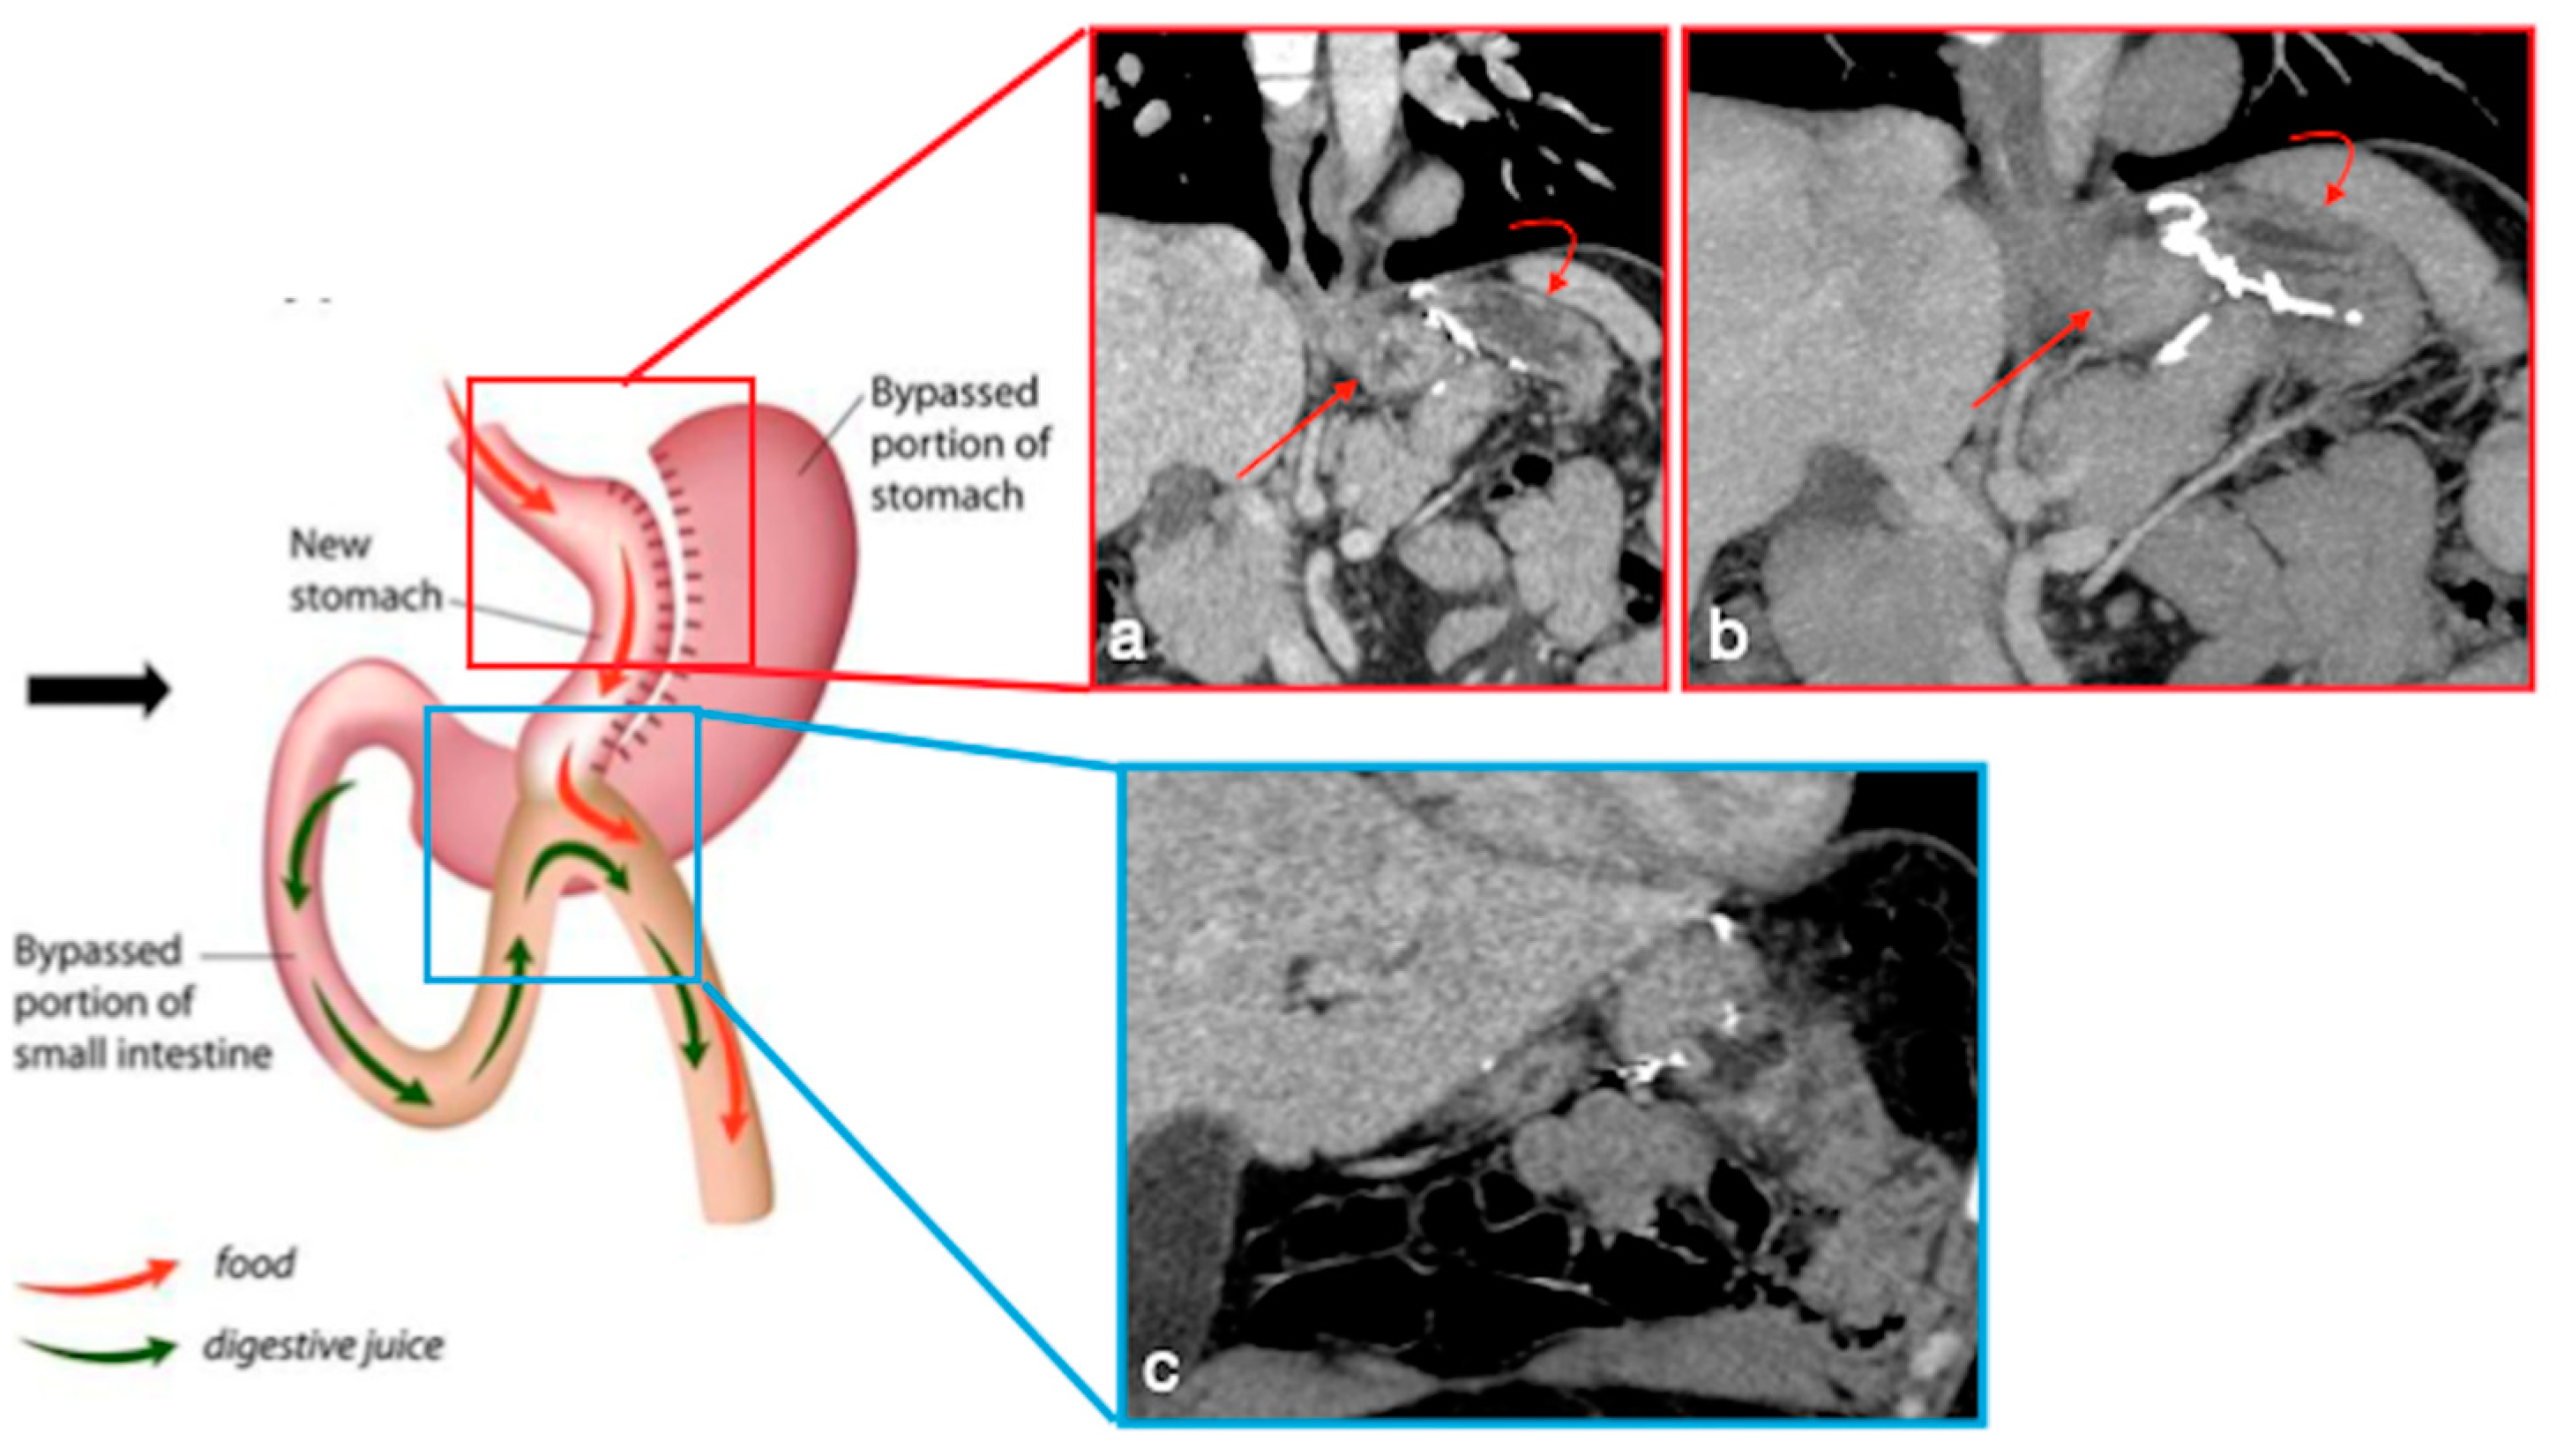

Figure 5. Gastric bypass. Surgical sutures seen at CT. Gastric pouch with gastrojejunostomy (a,b axial oblique view) and excluded stomach (b, arrow). Roux limb (c, coronal oblique view) of length of 75 to 150 cm from the jejunal division point for an average of 120 cm, jejunojenuostomy (d, circle, coronal view) between the biliopancreatic limb and the distal segment of jejunum (roux limb). The scheme was adapted from https://www.uptodate.com/contents/image/print?imageKey=GAST%2F79256 (accessed on 23 October 2022).

In RYGB, the transit of food along the gastrointestinal tract is rerouted to achieve a reduction in the absorptive capacity for calories. A small gastric pouch results from a surgical exclusion of the remnant stomach, followed by a gastrojejunostomy (between the new gastric pouch and the jejunum: alimentary limb) and a jejunojejunostomy (between the duodeno–jejunum channel and the jejunum–biliopancreatic limb), placed in communication in a common channel further downstream (Figure 5) [4,6].